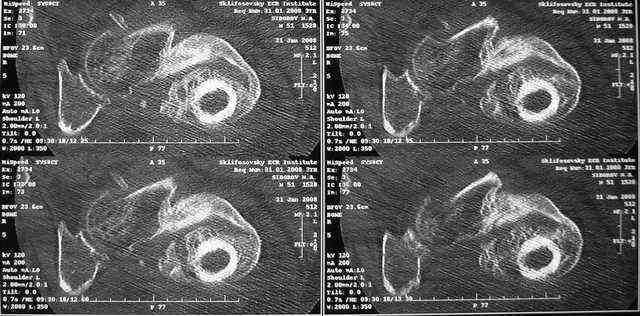

Какие были движения в суставах до наложения аппарата? Нет ли КТ с 3D?

Дорогие Александр Николаевич и Алексей Владимирович, вы конечно же правы. Если планировать остеосинтез, то надо сделать более точную репозицию. Планируем этим заняться в ближайшие дни. Алексей Владимирович, движения в тазобедренном суставе были в пределах 10-20 гр. Завтра попрошу у врачей из КТ сделать 3D реконструкции.

Очень признателен Вам за ответ, но позвольте мне не согласиться с Вами. Я бы пока не делал вывод о анкилозировании тазобедренного сустава. На рентгеновских снимках, да и по данным компьютерной томографии (а этот метод один из самых современных и информативных), хорошо прослеживается постоянной ширины щель между головкой бедренной кости и вертлужной впадины. Кроме того, несложно увидеть разницу "шеечно-диафизарного угла" до и после выполнения тракции в аппарате. Хотя, Алексей, даже если я и прав, это не сильно облегчает нашу задачу.